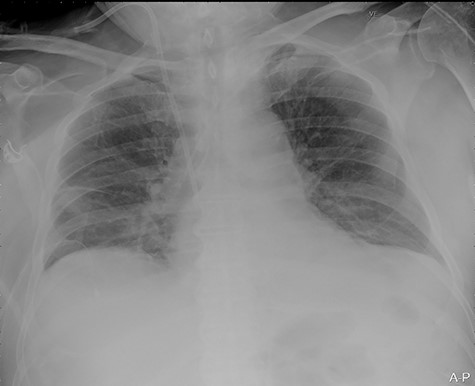

Our surgical team was contacted after 4 h, as the pleural fluid had become grossly haemorrhagic. A CXR showed haemothorax (Fig. 2). Upon clinical deterioration, the patient was intubated, and a 24Ch chest tube was introduced. Approximately, 500 ml of blood was immediately drained, followed by 300 ml during the first 30 min. ICA laceration was suspected. Despite transfusion of red blood cells and plasma and infusion of noradrenaline, the patient remained circulatory unstable. A new CXR showed massive haemothorax despite drainage (Fig. 3). The patient was now utterly haemodynamically unstable and not suited for transportation. As there are no thoracic surgeons or interventional radiologists in our hospital, the general surgeons decided to take him to the operating theatre. A wide anterolateral right thoracotomy was performed with patient lying in left lateral decubitus position. The right pleural cavity was full of fresh and coagulated blood. The pulsating bleeding was seen coming from the posterolateral, caudal chest wall, but the exact site deep down in the sharp costophrenic angle could not be localized and was inaccessible for any surgical haemostatic manoeuvre.

Portable chest X-ray in half-upright position showing haemothorax 4 h after placement of pigtail pleural drain.